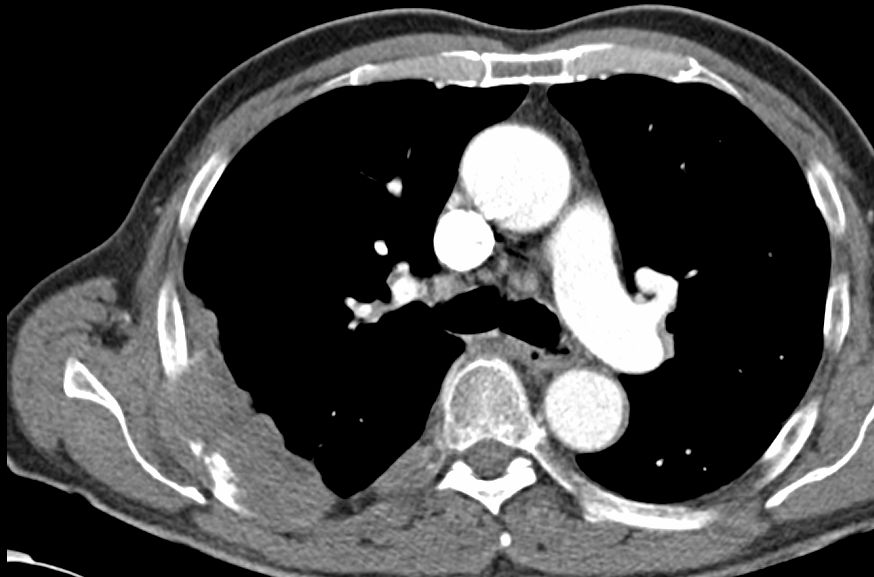

| Fallbeispiel | 63-jähriger Mann, bei dem ein rechtsseitiger Pleuraergusses auffiel.

![]() |

Im Oberbauch ein schmaler Aszitesrand um die Leber erkennbar. Histologisch epitheloides Pleuramesotheliom mit Peritonealbefall (im CT nicht erkennbar).